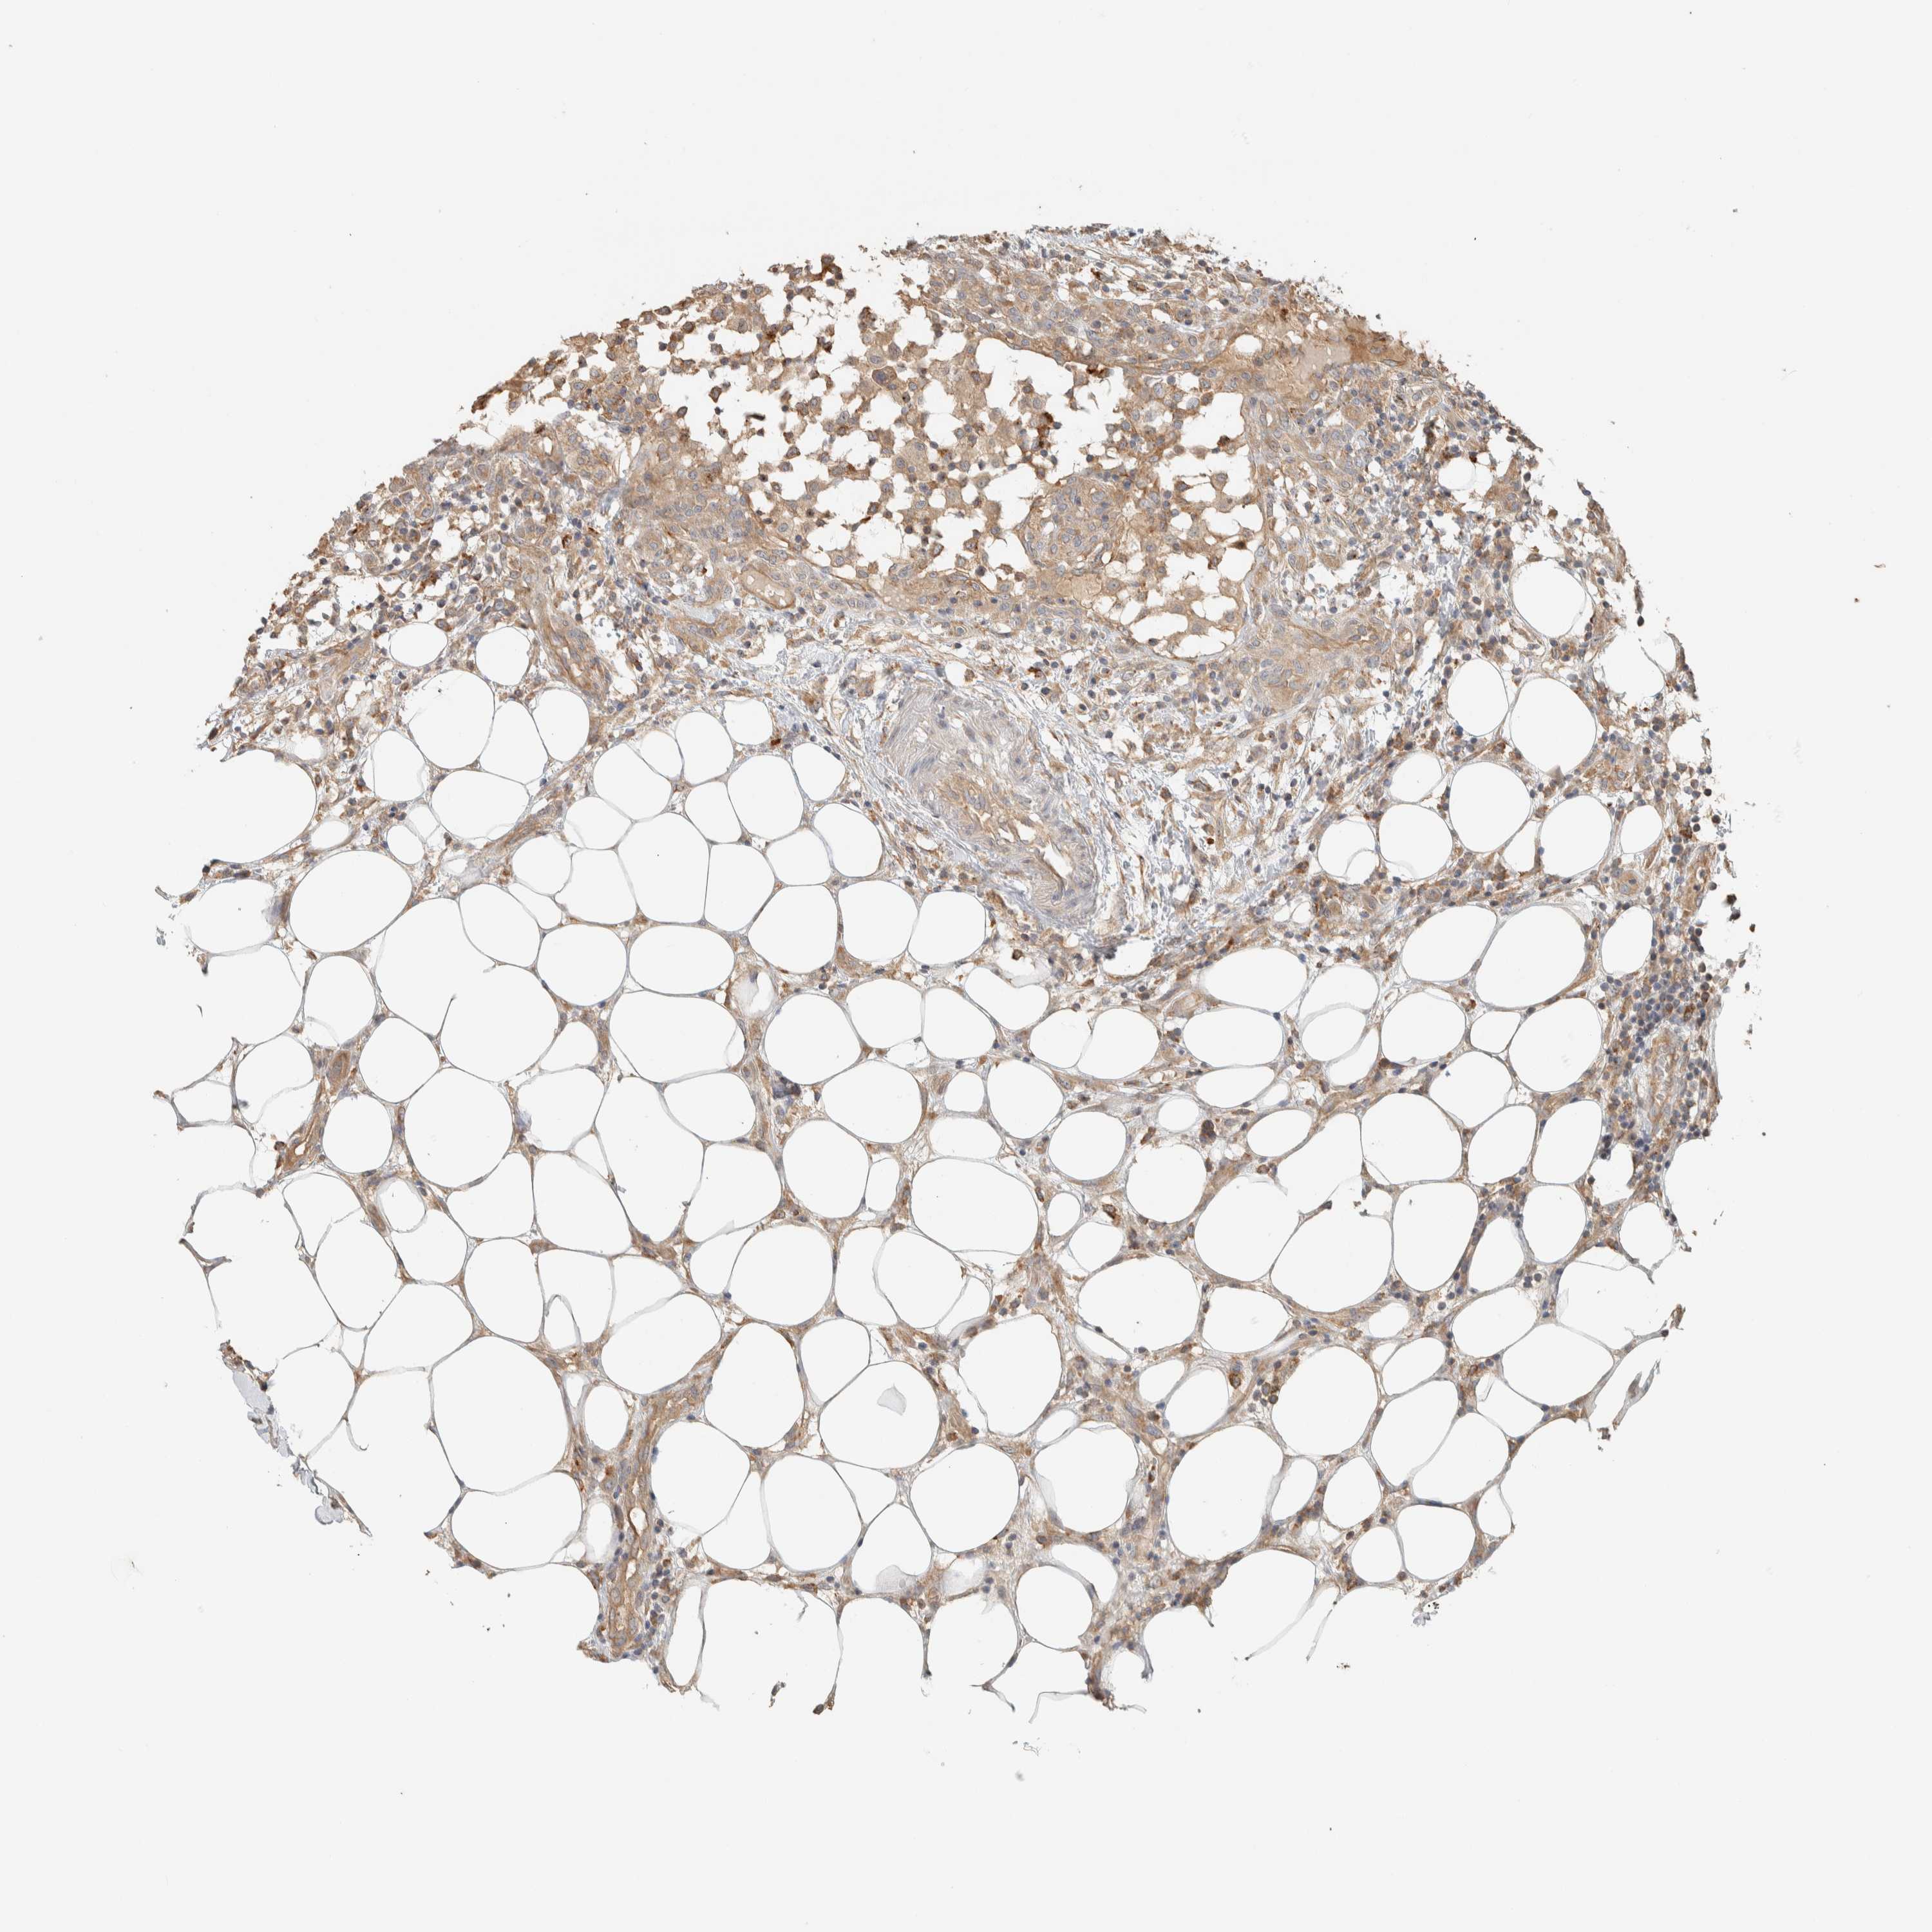

CANCER BREAST CANCER Show tissue menu

Breast cancer

Human cancer